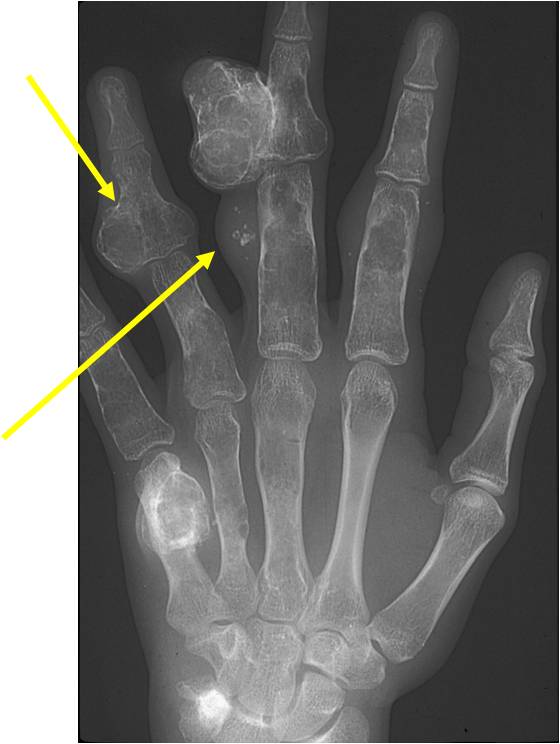

- 50% involve hands and feet (mostly phalanges)

- Localized, radiolucent defect usually with punctate calcifications

- Calcifications are stippled, punctate, popcorn like calcifications and “Ring and Arc” calcifications

- Cortex may be scalloped and thinned in the phalanges

- Geographic lytic lesion

- Expansile remodeling with thinned cortex

- Chondroid matrix with calcifications in majority of tumors

- Digits: Impending or actual pathological fracture

- Intralesional curettage and bone graft or cement